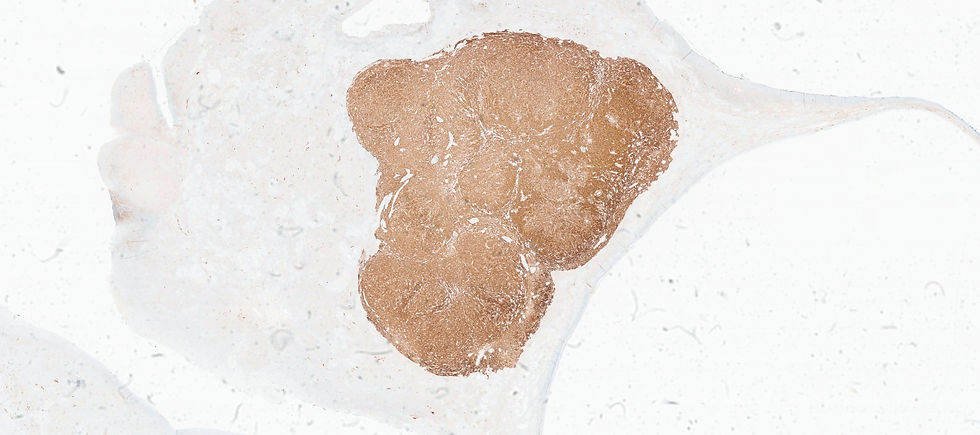

A panel of two stains are showed below. What's the diagnosis?

reticulin

Inhibin

The final answer is F. Adult granulosa cell tumor (AGCT). AGCT can show various morphological patterns however, the most common pattern is diffuse, but cells may be arranged in cords or trabeculae; large solid nest, or forming microfollicular pattern with Call–Exner bodies. Nuclei groove is a reliable feature but it is not always seen. In this case of luteinized tumor show abundant eosinophilic cytoplasm and often lack nuclear grooves. The tumor cells are positive for FOXL2, calretinin, inhibin (although staining may vary in distribution and intensity), and SF1. Reticulin surrounds groups of cells rather than single cell in thecoma or fibroma.